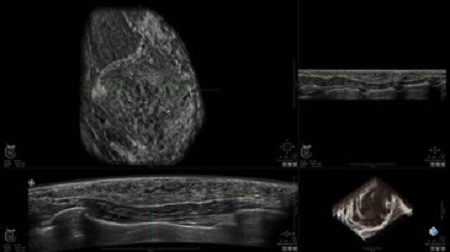

УЗИ-аппарат

GE INVENIA ABUS 2.0

GE INVENIA ABUS – это современный УЗИ аппарат, который создан для точной и эффективной диагностики сканирования с высокой плотностью молочных желез. Выявляемость патологий раковых и предраковых стадий заболевания составляет 55%, что в конечном счете позволяет ставить врачу точные и своевременные диагнозы. Традиционные методы использования маммографии не показывают такой выявляемости, ограничиваясь лишь 3-38%.

УЗИ-аппарат GE INVENIA ABUS позволяет проводить максимально операторонезависимые процедуры, что значительно снижает риск неправильной постановки диагноза и сопутствующие издержки на обработку информации. Система готовит отчет в течение 3-х минут после сканирования, это безусловное преимущество по сравнению с обычным УЗИ сканером.

• датчик с изогнутой апертурой для качественного исследования

• сканирование одной грудной железы в трех проекциях не более 60 сек.;

• обработка результатов за три минуты.

Данное устройство классифицируется, как стационарное, используемое в многопрофильных клиниках, женских консультациях, медицинских центрах. Вес без учета дополнительного оборудования составляет 105 кг. Удобная колесная база позволяет оперативно маневрировать в ограниченных пространствах, в том числе передвигать устройство в коридорах клиники. Большой 17-ти дюймовый монитор с широкими углами обзора выводит максимально качественную картинку в формате Full HD.